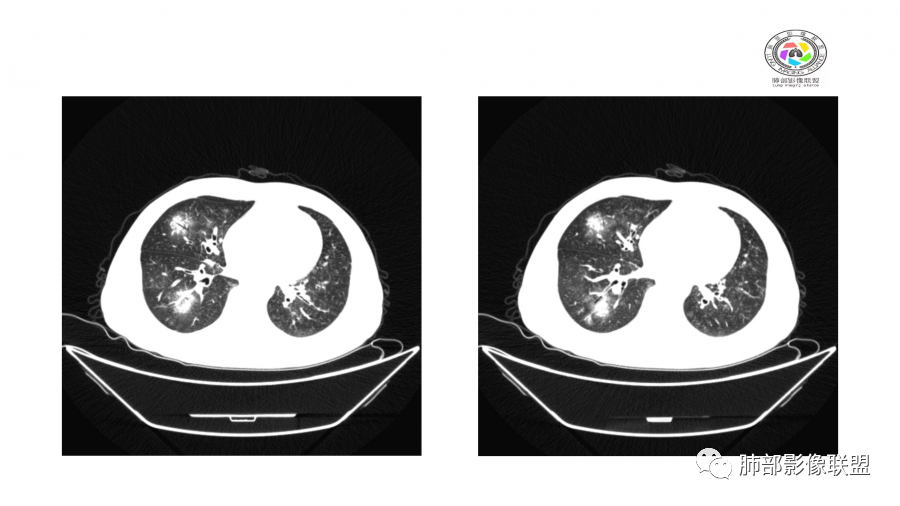

10天后:病灶继续吸收好转

伴随少量胸水

应该与气道无关

符合间质、血管来源病变

此起彼伏

有肾功能不全

支持与肾病相关

警惕血管炎